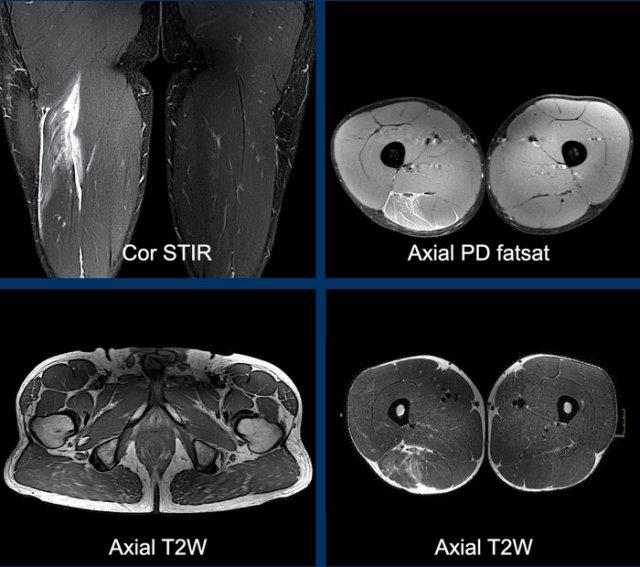

MRI protocol based on pulse sequences: coronal fatsat, axial PD fatsat and axial T2.

- Chuỗi xung T2 xóa mỡ mặt phẳng coronal (fatsat, STIR hoặc dixon) cho phép đánh giá tổng quan nhanh chóng về tổn thương và giúp đo lường dễ dàng các khoảng cách liên quan (ví dụ: chiều dài vùng phù nề hoặc mức độ co rút gân).

- Chuỗi xung PD xóa mỡ mặt phẳng axial (fatsat hoặc dixon) tập trung vào vùng tổn thương và cho phép đánh giá đầy đủ tình trạng phù nề hoặc tụ máu, bao gồm cả trong cơ lẫn giữa các cơ.

- Chuỗi xung T2 mặt phẳng axial từ điểm nguyên ủy đến điểm bám tận cho phép hiển thị chi tiết tổn thương gân. Các hình ảnh độ phân giải cao này rất hữu ích để đánh giá giải phẫu và mức độ tổn thương trên từng bó sợi riêng lẻ. Thông thường cần hai khối chụp (stack).

Toàn bộ phức hợp cơ hamstring của cả hai chân cần được khảo sát trên tất cả các chuỗi xung để so sánh bên tổn thương với bên hamstring lành.